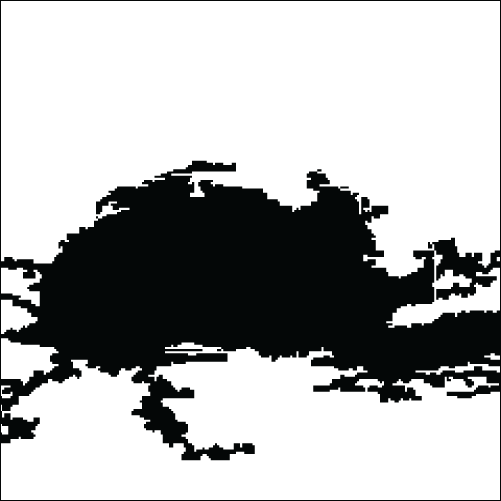

In the sequence of processing ultrasound images, Fig. 20 shows the original input image acquired from an ultrasound scan from the dataset provided in [41]. This image is subsequently resized for standardization, as illustrated in Fig. 21, to maintain consistency throughout all following processing processes. Next, Fig. 22 shows the filtered version of the picture, which has been filtered bilaterally to minimize noise while keeping critical edge details required for accurate anatomical structure detection. Fig. 23 shows further picture enhancement using the Non-Local Means (NLMS) filter, a method chosen precisely for its ability to preserve detailed details while increasing contrast. Finally, Fig. 24 shows the contour of the tumor, which clearly defines the afflicted area and serves as an input for feature extraction and subsequent classification stages.

Figure 24: Contour of tumor